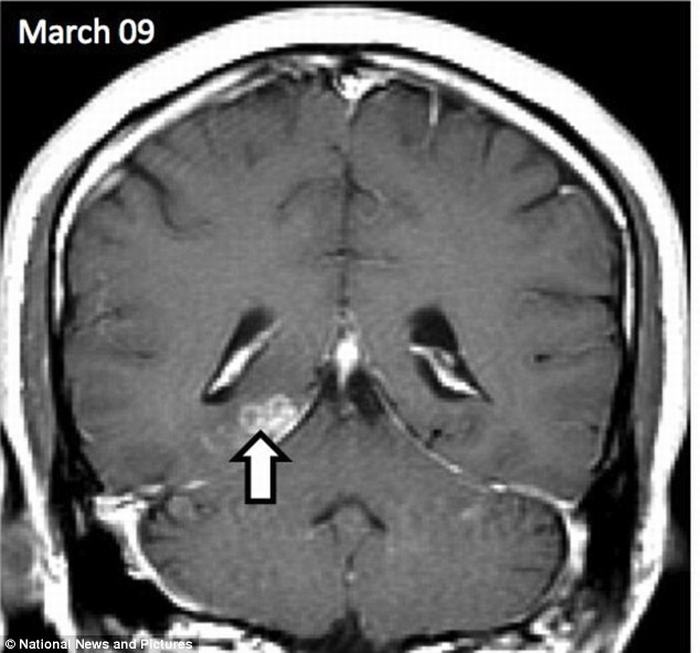

| Con sán đã ‘du lịch’ khoảng 5cm từ phía bên phải sang bên trái của não người đàn ông này trong suốt 4 năm. |